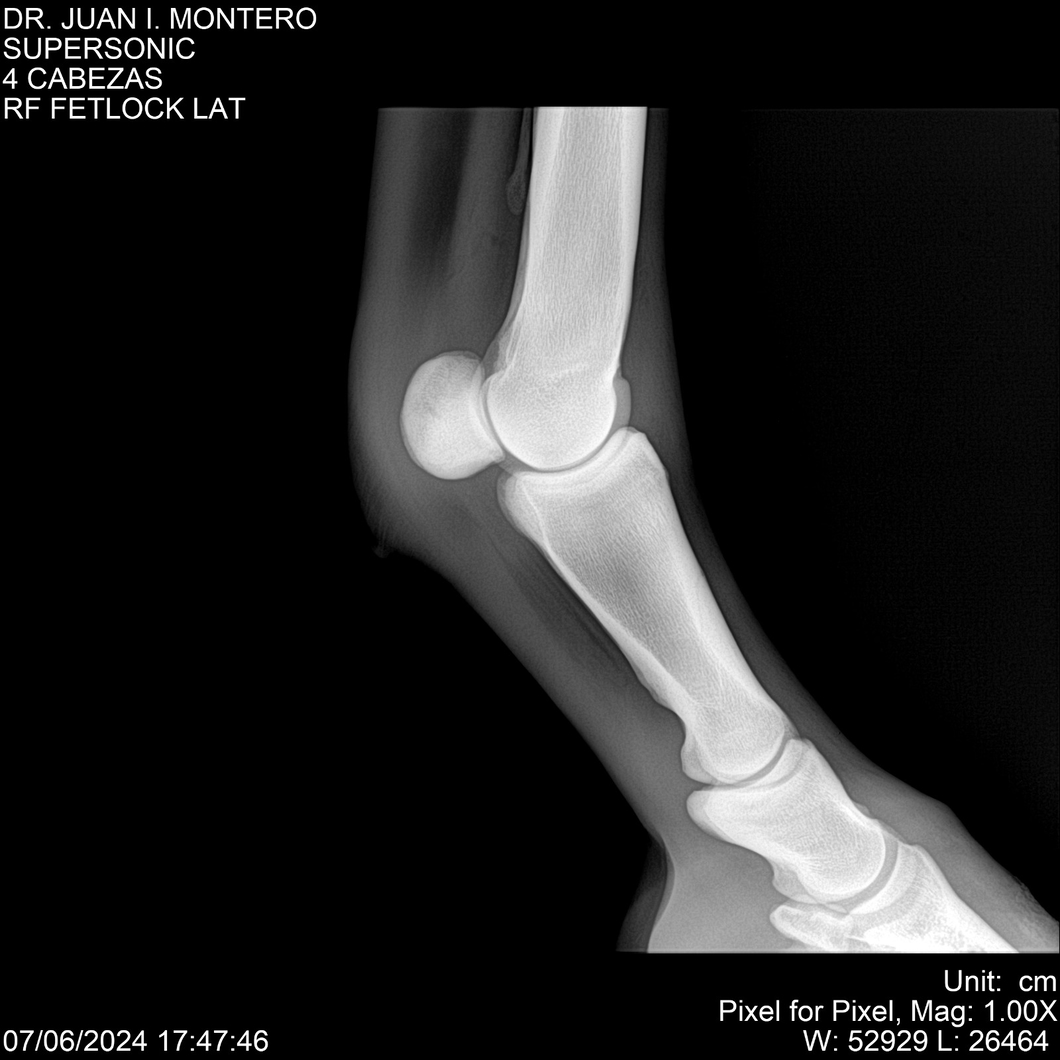

LOTE 5, SUPER SONIC Lote Anterior Volver al remate Lote Siguiente Ficha Contacto Montevideo - Ficha del Lote Identificador: #281089 Categoría: Yeguarizos Montevideo - 69 Visualizaciones ClicData Contacto Empresa: Abelenda N. R., Walter Hugo Nombre*: Teléfono* : E-mail* : Mensaje Enviar Registrese gratis Este contenido Exclusivo está disponible sólo para usuarios registrados Ingresar